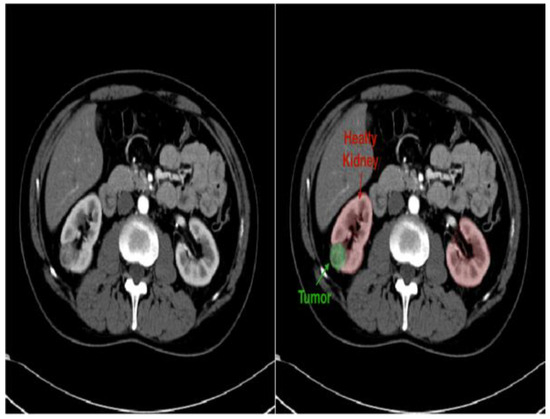

- Improved diagnostics: AI-driven image analysis tools can enhance the identification and description of pediatric kidney cancers and tumors. Radiologists can spot minor abnormalities, characterize renal masses, and estimate tumor burden more accurately using ML algorithms that have been trained on large datasets of pediatric renal images (Figure 7). AI algorithms enable the early identification of kidney cancers and tumors by methods including pattern recognition, masking, segmentation, and quantitative analysis, allowing for confident diagnosis and timely treatment [24].